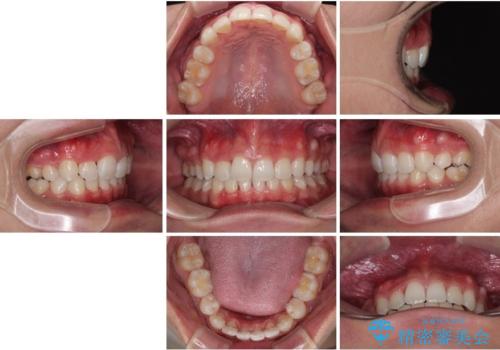

抜歯矯正で叢生と正中のずれを改善|審美装置による矯正症例

- 今回ご紹介するのは、

「全体的なデコボコ(叢生)」「上下の正中のずれ」 を主訴として来院された20代男性の患者様の症例です。

叢生が強く、歯が並ぶスペースが不足していたため、

上下左右の第一小臼歯を抜歯して、矯正治療のための適切なスペースを確保する計画としました。

上顎左側第一大臼歯に齲蝕が認められたため、矯正治療終了後に 精度の高いセラミックインレー にて修復治療を行いました。